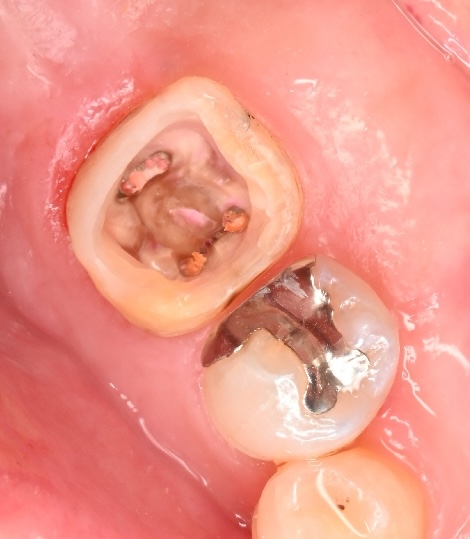

3. ここでようやく「土台作り」です

むし歯を全てきれいに取りきると、歯の壁(縁)が大きく失われた状態になります。 このままでは、治療中に唾液が入り込んだり、仮の蓋がすぐに取れたりしてしまいます。

そこで行うのが、今回のテーマである**「隔壁(かくへき)」**の作製です。 コンポジットレジン(歯科用プラスチック)を用いて、失われた歯の壁を復元します。

建築現場でいう「基礎工事」のようなもので、これにより治療に適した清潔な環境が整います。